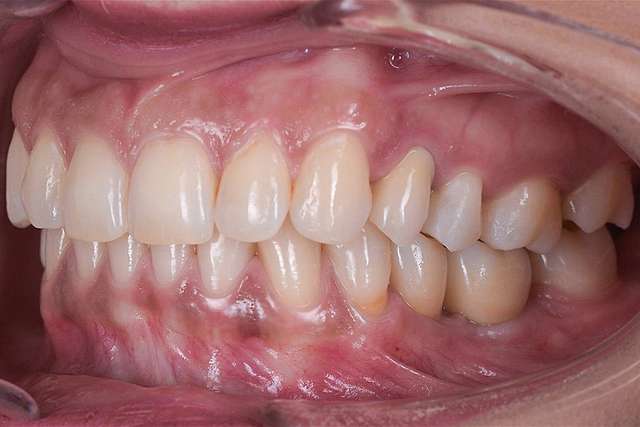

Guided surgery, for one, facilitates an ideal pre-planned position, in relation to available bone, and even more important, in relation to the future implant supported crown. Guided surgery translates into increased precision, which means safer surgeries, reduced surgery time, and reduced trauma. Also the focus of these types of treatments is shifted towards tissue reconstruction, which on the long run, has a far greater impact esthetically and biologically. Tissue stability means implant longevity. This case is a relevant example for this type of approach towards implant dentistry.